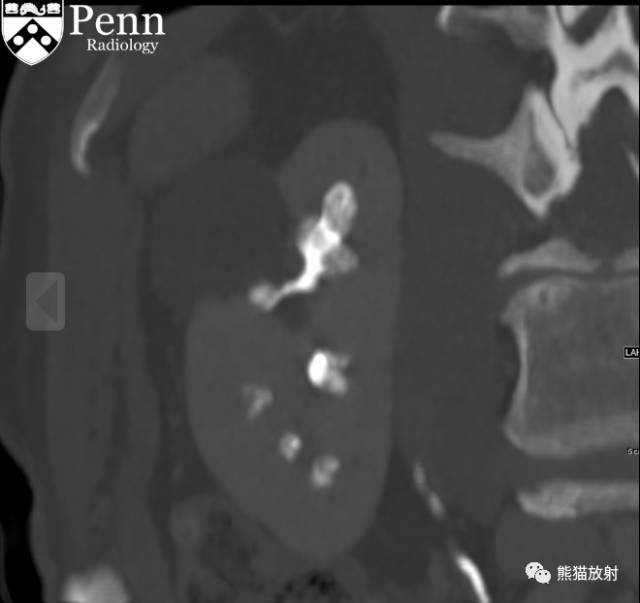

Scout, coronal precontrast, axial nephrographic/excretory phase images, and volume-rendered coronal reconstructions of the left and right kidneys are shown below.

定位像、冠状平扫、轴位排泄期图像及左、右肾冠状VR重建如下所示。

CT urogram (2017): Noncontrast images demonstrate multiple bilateral nonobstructing renal calculi, the largest measuring 6 mm in the right kidney. Some of the calcifications could represent nephrocalcinosis — for example, those in the upper pole of the right kidney. The kidneys show symmetric enhancement without suspicious renal mass. Multiple bilateral exophytic simple renal cysts are noted, the largest in the midpole of the right kidney measuring 3.6 x 4.3 cm. There are additional subcentimeter low-attenuation lesions that are too small to characterize. There is a “paintbrush sign” appearance to the renal medullae in keeping with a history of medullary sponge kidney. There is mild bladder wall thickening and trabeculation that may be related to chronic outlet obstruction. Further evaluation is deferred to cystoscopy.

CTU:CT平扫可见双肾多发非梗阻性肾结石,右肾最大者直径约6mm,其中一些钙化可能代表肾结石,例如,右肾上极的那些。肾脏对称性强化,未见可疑肾肿物。双肾可见多发单纯性肾囊肿,大者位于右肾中部,大小约3.6 x 4.3 cm;另可见不足1cm的低密度灶,其太小而不能显示。肾髓质表现为“毛刷征”,符合髓质海绵肾。膀胱壁轻度增厚并小梁形成,与慢性流出道梗阻有关。进一步评估需膀胱镜检查。